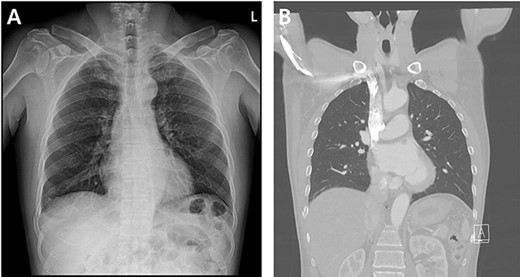

A 59-year-old man was admitted with multiple rib fractures and liver contusion due to a fall injury. He was standing on a chair for working at a farm, and it was knocked over causing him to fall and hit his flank against the corner of the chair. There was continuous pain while resting at the right flank and severe pain with pressure was noted, but no external wounds or bruises were observed. There were right 7th–11th rib fractures, scanty pneumothorax, minimal hemothorax and a 2-cm-sized liver contusion in abdomen and chest computed tomography (CT) scan (Fig. 1A, B). He was hospitalized for pain control and close observation in the general ward, and conservative management was initiated. Also, no significant changes were noted in the following daily follow-up chest radiographs. The patient suddenly complained of right-sided chest and back pain aggravation, cold sweating and fatigue 80 h after the traumatic injury. His mental status was alert, but v/s including systolic blood pressure (SBP) of 100–120 mmHg, heart rate (HR) of 40-60 beats/min and oxygen saturation of 100% during the admission changed to an SBP of 86/60 mmHg, HR of 88 beats/min and oxygen saturation of 97% when the symptoms occurred. Chest radiography was performed after the patient experienced aggravated symptoms, such as right-sided flank pain, cold sweating and fatigue. Compared to the previous scans, signs of increased opacification and peribronchial and parenchymal infiltrations were observed, which were indicative of hemothorax (Fig. 2A, B). We performed enhanced dynamic chest CT to identify any presence of active bleeding. On the chest CT scan, a large amount of hemothorax was identified in the right lung field along with multiple fractures of the right ribs. However, there were no signs of contrast leakage indicative of active bleeding (Fig. 3). Hemoglobin levels decreased from 13.1 g/dl on the day before the symptoms appeared to 11.5 g/dl at the onset of symptoms and to 9.4 g/dl after 2 h. Four packs of RBC transfusion and fluid were administered to the patient, and he was moved to the intensive care unit for close monitoring. And tube thoracostomy was performed, and 1600 ml of fresh blood was drained (Fig. 4A). The following day, 500 ml of blood was drained through the chest tube, but his v/s were stable (Fig. 4B). The amount of bleeding through the chest tube was decreased, but the drained fluid was fresh blood. And we thought that the remaining hematoma was not effectively drained, so the patient’s respiratory discomfort could persist and cause uneffective ventilation. And then we consulted with the Department of Thoracic Surgery, and video-assisted thoracoscopic surgery (VATS) exploratory thoracotomy was performed to identify the bleeding source caused by displaced rib and evacuate the large amount of hematoma. There was a large volume of hematoma within the pleural space and between the right lower lobe, diaphragm and fissure, but no active bleeding point was located. The fractured right 10th rib pierced through the pleural space and was displaced to the thoracic cavity, which was easily reduced. There was no injury surrounding the diaphragm, and although the general lung and chest wall contusions were severe, there were no signs of lung parenchymal lacerations (Fig. 5A–C). Chest tube drainage was serous, and there was no further bleeding. There were no signs of bleeding or any other abnormal findings on chest CT performed at the outpatient clinic, and the patient had no complaints of any symptoms (Fig. 6A, B).

Radiographic findings. (A) Initial chest X-ray showed no evidence of hemothorax. (B) Initial chest CT also showed no evidence of hemothorax.